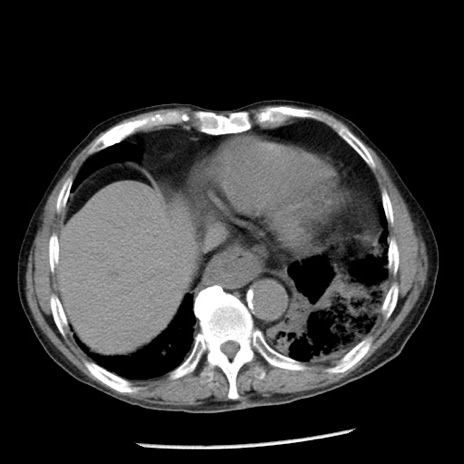

症例26(横断像)

【症例】80歳代男性

【主訴】嘔吐

【現病歴】昨晩2回嘔吐あり、今朝になっても嘔吐あり。来院。

【既往歴】胃潰瘍

【身体所見】意識清明、BT 37.6℃、BP 166/95mmHg、HR 100bpm、SpO2 97%、腹部:平坦・軟、腸蠕動音聴取良好、圧痛なし。

【データ】WBC 21900、CRP 1.46